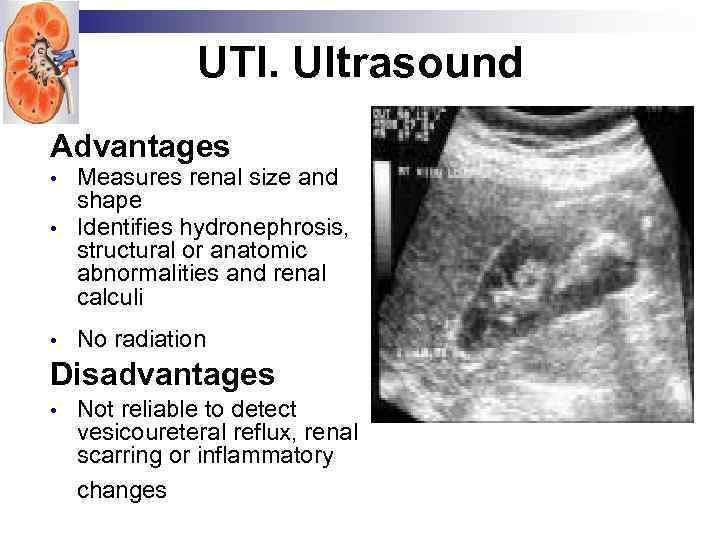

UTI. Ultrasound Advantages • Measures renal size and shape Identifies hydronephrosis, structural or anatomic abnormalities and renal calculi • No radiation • Disadvantages • Not reliable to detect vesicoureteral reflux, renal scarring or inflammatory changes

UTI. Ultrasound Advantages • Measures renal size and shape Identifies hydronephrosis, structural or anatomic abnormalities and renal calculi • No radiation • Disadvantages • Not reliable to detect vesicoureteral reflux, renal scarring or inflammatory changes